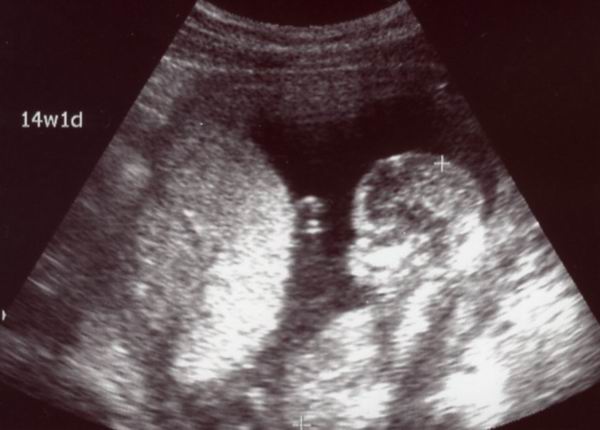

午前中,定期健診に行ってきました。

現在15週,あと1週間で5ヶ月(いわゆる安定期)に入ります。

早速ですが,エコーはこちら。

今日は右側に寄りかかっているようなポーズで写ってくれました。

今日の感動その1。

静止画だと分からないんですけどねー,モニターを通して

動画の状態で見ると,お腹の中で結構動いてるんですね。

今日も見ている目の前でぴくんと動いたり,くるんと回ったり

してました。元気で順調だそうです(*^_^*)

もうちょっと育ってくると,胎動として私の身体でも感じられる

そうですよ。

「あっ,動いた!」ってやつよね。楽しみー♪